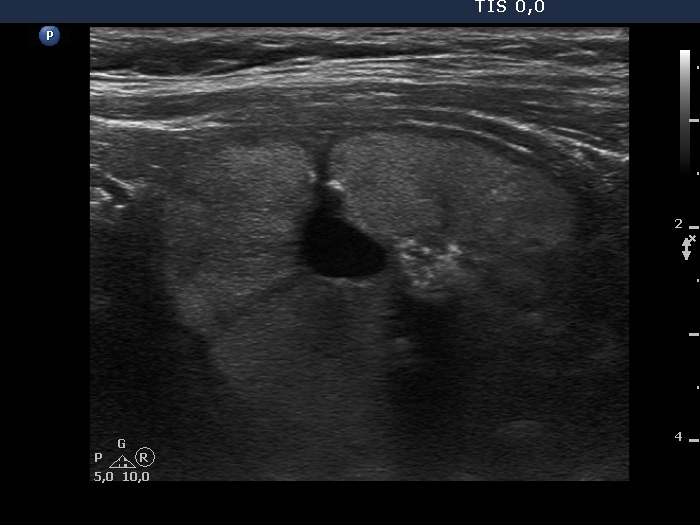

Benign cystic-colloid goiter (cytological diagnosis)

There are several pale granules and lines in the solid part of the nodule (left image), while the right image demonstrates the presence of posterior back wall enhancement figure in the dorsal wall of the small cystic areas.